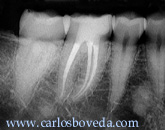

Molar Inferior Derecho

El

paciente es referido a nuestra consulta para

tratamiento endodóntico del primer molar

inferior derecho. Su Odontólogo nos refiere

que eliminando una lesión de caries en este

diente se encontró con una franca

exposición pulpar del cuerno

mesio-vestibular. En ese momento se le

colocó un algodón con eugenol y un

cemento provisional (IRM).